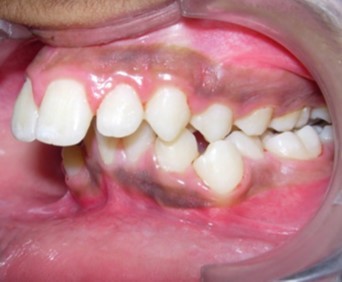

Intraoral assessment. (Figure 1d,Figure 1e,Figure 1f,Figure 1g,Figure 1h).

Figure 1f.Pre-treatment intra-oral-Left

The maxillary arch was V-shaped with severely proclined and rotated maxillary incisors with a palatally placed 12. The mandibular arch was U-shaped with severe crowding of mandibular incisors, with 43 partially erupted and buccally placed with transpositioned 42 and 43, with 42 mesiolingually rotated, 33 distolingually rotated and 34 distolingually rotated and buccally placed.

Severe increase in overjet and deep bite were both observed. The maxillary midline coincided with the skeletal midline but the mandibular midline was shifted to the right side by 1 mm. Bilateral maxillary posterior crossbite was also observed. On right side the molar relation was Class I and on the left side it was Class II. The canine relation was Class II on the left side and the curve of Spee was increased.